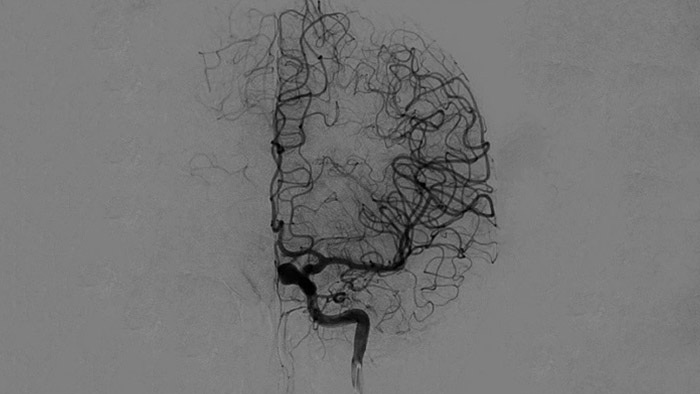

Imágenes nítidas con angiografía de sustracción digital (DSA) 2D con tecnología ClarityIQ

DSA 2D con tecnología ClarityIQ

ClarityIQ aplica la compensación automática del movimiento durante la angiografía de sustracción digital (DSA) en tiempo real para mantener imágenes nítidas de los vasos. Esto respalda la toma de decisiones fundamentadas durante los procedimientos de accidente cerebrovascular.